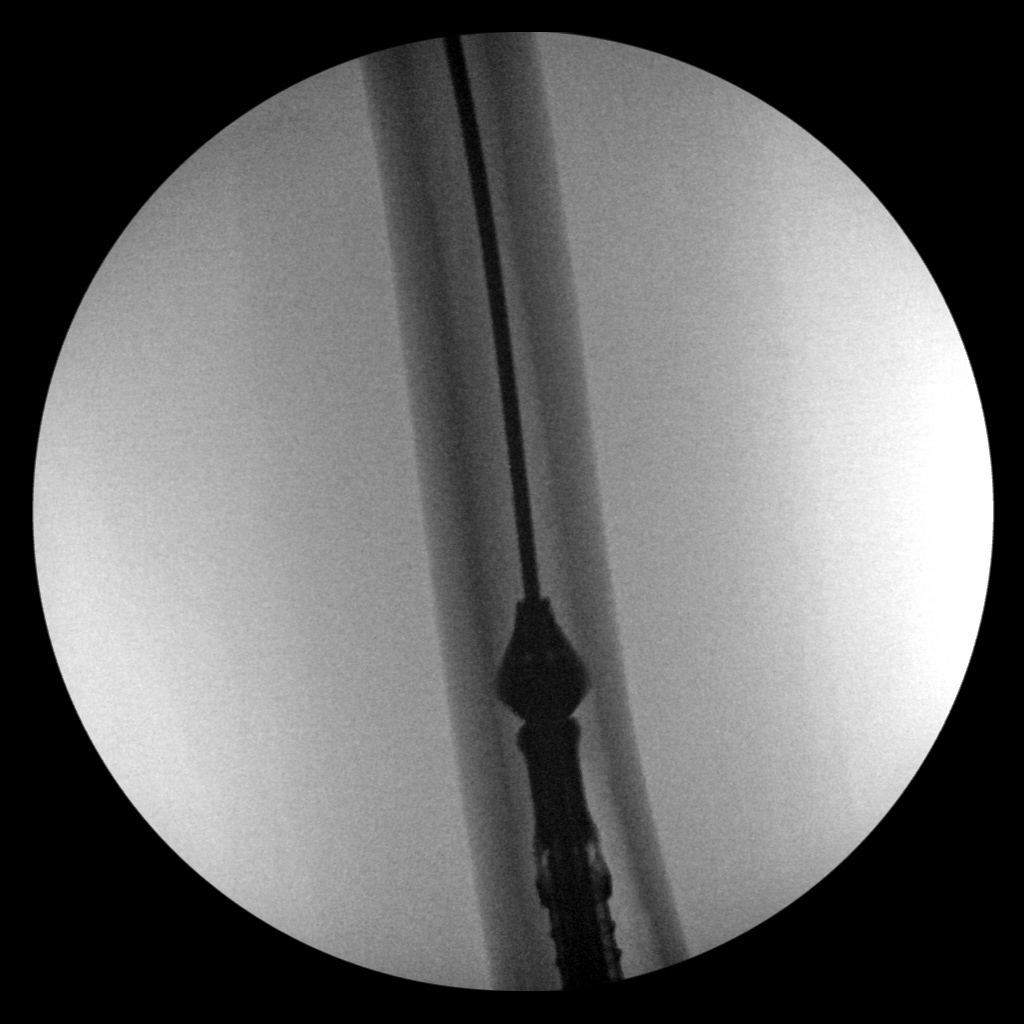

41 year-old woman with left distal tibial pilon fracture with considerable bone loss. Bone graft harvesting to replace the lost bone was done from the left femur using a DePuy Synthes RIA intramedullary bone graft harvest system. The left two images show the reamer in the left femur. The right two images show postoperative gas (arrow) from the bone harvest site. Courtesy Kellon Hansen, MD.

Bone graft harvesting

Bone graft harvesting Bone graft harvesting Bone graft harvesting postoperative image Bone graft harvesting postoperative image